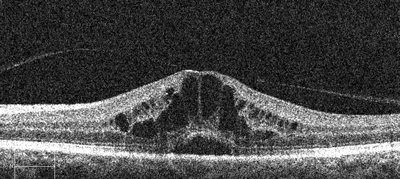

Diagnosis of this painless condition is made through observation of swelling or thickening of the central retina (at the macula) and can be determined through either direct observation, the invasive technique of fundus fluorescein angiography or through the newest innovation to assist in the detection of this disorder, optical coherence tomography (OCT).

Slit-lamp biomicroscopy reveals an irregular foveal light reflex, retinal thickening and / or intraretinal cysts in the foveal region whilst the findings observed with fundus fluorescein angiography and OCT show characteristic appearances associated with the disorder. The advent and utilisation of OCT technology which provides high resolution, cross-sectional and real-time images of the macula region has heralded an increase in the sensitivity and specificity of the detection of the condition. The incidence of cystoid macular oedema being reported using OCT is as high as 14% in post-cataract patients [7]. This increase in sensitivity in the diagnosis of the disorder provides support for the routine use of this non-invasive, objective measure in the assessment of post-cataract patients. Moreover, it could be argued that the specificity in detection would be further enhanced if OCT was conducted both pre and postoperatively, in the case of adequate imagery being possible in the presence of any lenticular opacity. Using this objective measure in this way would help to ensure the correct diagnosis of the disorder, and to rule out the presence of pre-existing macula disease that may not be detectable through direct observation, but that may be mistaken for forms of Irvine Gass Syndrome post-surgery. Indeed this is supported by some members of the ophthalmology community to assist in improving patient care and allowing for improved counselling and management of patient expectations post-surgery [8].

Figure 1: Typical case of Irvine Gass Syndrome as seen using a) biomicroscopy, b) optical coherence tomography (OCT), and c) fundus fluorescein angiography (FFA). (Images provided by the author)